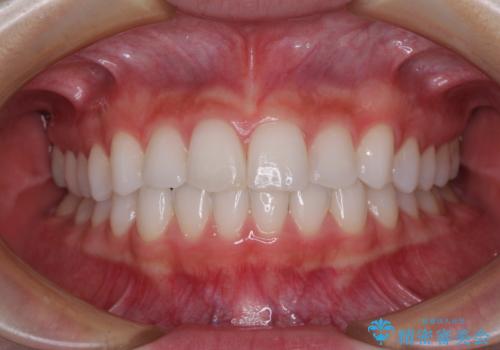

矯正治療は8ヶ月ほどで終了し、速やかに虫歯治療に移行することができました。

保険治療で用いる樹脂(コンポジットレジン)で行った虫歯治療は、周辺が変色して汚くなっていましたが、下顎はセラミックインレーで審美的に、上顎はPGAインレーで歯に負担の少ない治療を行うことができました。

- 歯並びと虫歯をきれいにしたいとのことで来院された患者様です。

楽して短期間で歯列を整えたいとのことで、ワイヤー装置を用いて矯正治療を行い、矯正治療後に下顎の虫歯はセラミックインレー、上顎はPGAインレー(ゴールドインレー)、根管治療を行う歯についてはオールセラミッククラウンにて補綴治療を行うこととしました。

- 20代女性